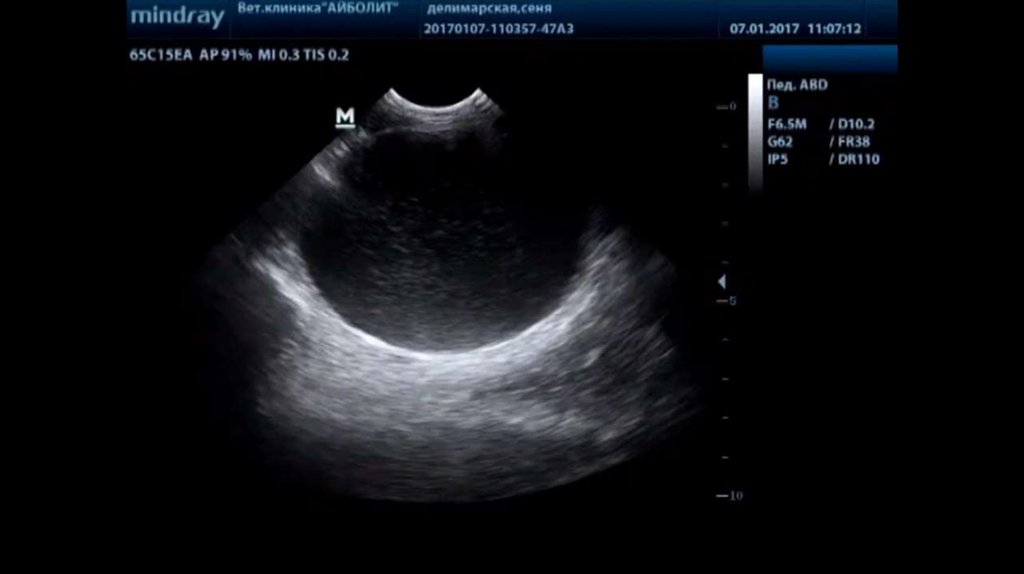

В клиниках назначают для подтверждения назначают общие

анализы крови и мочи, УЗИ, при возможности – бакпосев

мочи